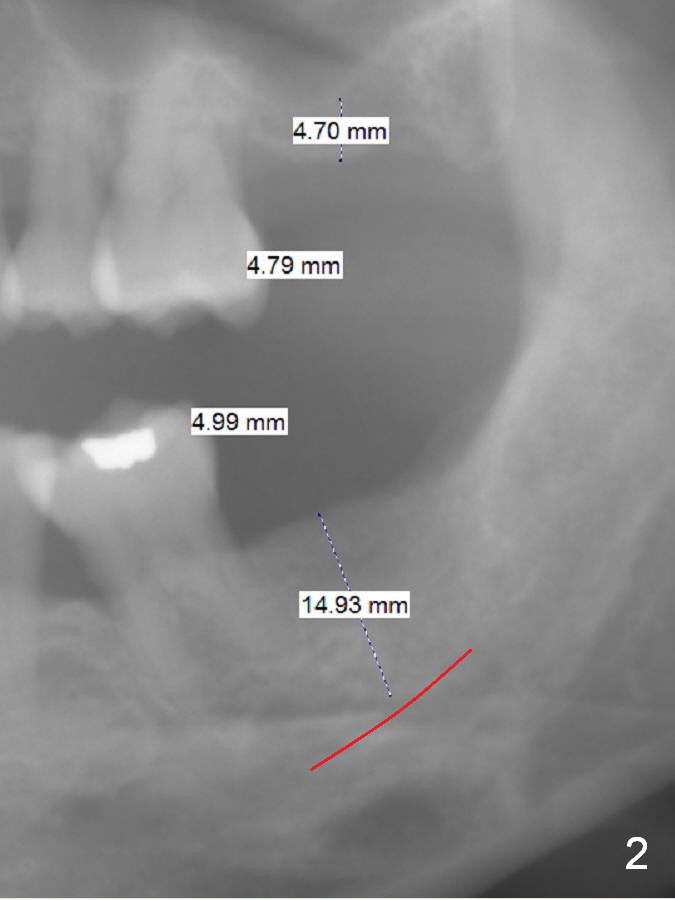

A 32-year-old woman is concerned about her upper anterior tooth flaring (Fig.1). She is eager for periodontal treatment. She masticates on the right side. The teeth #15 and 18 were extracted ~ 1 year ago. To lessen anterior flaring (take photos when she returns), implants are going to be placed at these sites (Fig.2,3). IBS and Magic Sinus Lift Kits will be used for #15. Magic Split gains access for 5 mm deep (gingival level), followed by ME 3 mm and next ME for 5 mm and Sinus lifter for 9 mm (bone level 7 mm, CMC). Or use the 4.3 mm drill from Magic Sinus Lift Kit for 5 mm, followed by Sinus Lifter for 9 mm. Insert PRF plugs into the sinus, followed by allograft (.5-1.0 mm) with Osteogen. If implant stability is low, place a healing abutment or screw.

For #18 implant placement, palpate the ridge to determine the width. Trim the ridge if it is pointed. Also use Magic split for access and bone density testing. Either BEB or PBR will be adopted.